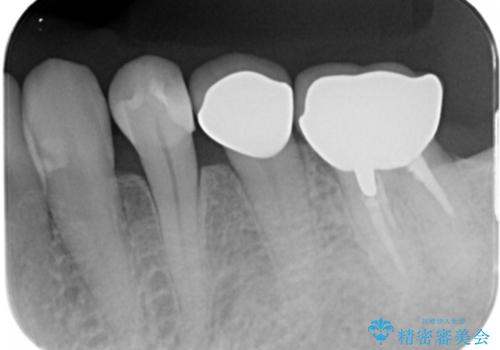

症状もなく、レントゲンでも根尖病巣が見られないため

患者様と話し合った結果、中の土台は外さず、被せ物のみのやりかえとなりました。

レントゲン上で根尖病巣が見られた場合

中の土台を外して根管治療を行わなくてはなりません。

また根尖病巣がなくて土台を変えたい(メタルから白の土台)場合

土台を外すと根管内が細菌感染する恐れがあるために根管治療をやり直す必要があります。